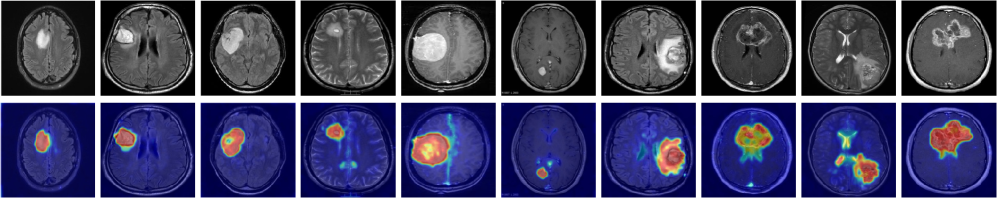

Here, we assess how well the features learned on industrial datasets generalize to domains far from the industrial domain. To this end, we evaluate Crane on seven medical datasets spanning diverse applications, including skin cancer detection in photography images, colon polyp identification in endoscopy images, thyroid nodule detection in ultrasound images, and brain tumor detection in MRI images. The goal is to determine whether the model has developed a broader understanding of normality and abnormality.

Table 1 presents the results, showing a consistent image-level trend: both versions outperform prior SOTA by a similar margin, improving average performance by 2.2% to 3.6% across reported metrics. At the pixel level in medical datasets, Crane outperforms existing models and remains competitive with AnomalyCLIP, while Crane+ further improves AUPRO by 5.0% and F1-max by 2.3% over the SOTA, demonstrating strong zero-shot generalization across challenging medical benchmarks.

Appendix D Visual Analysis

To provide an intuitive comparison, we present anomaly maps generated by the top competing models: VAND, AdaCLIP, AnomalyCLIP and both versions of our model, Crane and Crane+, across industrial images from MVTec-AD, VisA, MPDD, BTAD, DAGM, and DTD-Synthetic, as well as medical images from ISIC, CVC-ClinicDB, and BrainMRI. The training settings are detailed in the ’Experiment Settings’ section (5). Note that BrainMRI only has image-level labels, and the provided sample is annotated by a medical professional. As shown in the Figure 3, VAND suffers from high false positive rates (FPR), while AdaCLIP exhibits a high false negative rate (FNR). AnomalyCLIP improves sensitivity by reducing FNR but still struggles with high FPR. By leveraging stronger semantic correlations among patches, Crane reduces both FPR and FNR over previous methods, yielding tidyier and more precise results. This effect is further enhanced in Crane+, demonstrating superior localization performance.